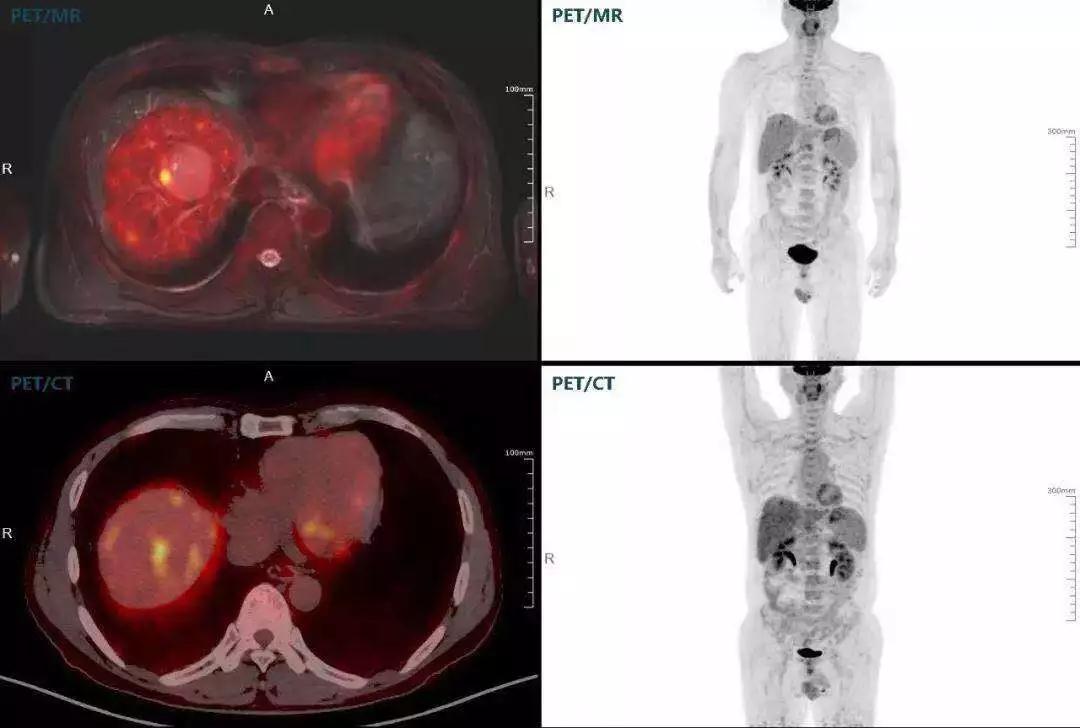

肝癌

聯(lián)影“時(shí)空一體”超清TOF PET/MR搭載的壓縮感知技術(shù),能夠同時(shí)實(shí)現(xiàn)16期成像,精準(zhǔn)捕獲肝臟動(dòng)態(tài)影像的每一瞬間,同時(shí)兼顧早期與晚期等全部期相的完整病灶信息,實(shí)時(shí)、全方位鎖定病灶。同時(shí),基于其2.8mm超高分辨率,能夠精細(xì)呈現(xiàn)腫瘤邊界信息,捕捉局部微小病灶與遠(yuǎn)端轉(zhuǎn)移灶,助力醫(yī)生精準(zhǔn)診斷。

(對(duì)于同一例肝臟惡性腫瘤,PET-CT與PET/MR成像對(duì)比。可以看到,聯(lián)影PET/MR圖像對(duì)腫瘤邊界和FDG高濃聚區(qū)域清晰顯示。)